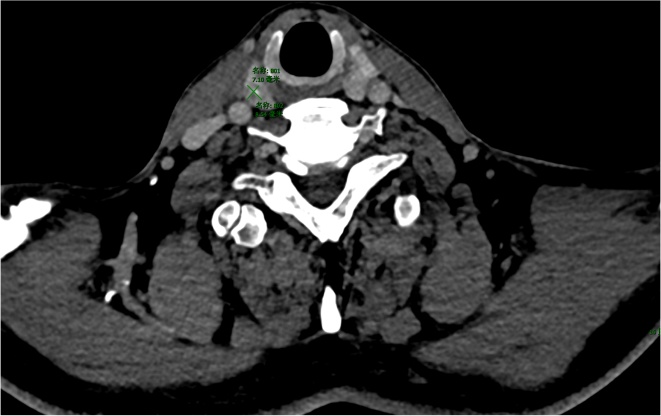

注:甲状腺增强静脉期(a)及相应ROI区域勾画(b)。

Figure 2. CT imaging of a 63-year-old male patient with thyroid follicular epithelial hyperplastic lesion

2. 男性63岁甲状腺滤泡上皮增生性病变患者CT影像

由2名具有6年以上甲状腺CT诊断经验的放射科主治医师采用联影URP组学软件在CT图像上分别逐层手动勾画ROI (图1图2),然后自动提取影像组学特征,通过组内相关系数(intraclass correlation coefficient, ICC)检验保留ICC ≥ 0.75的特征,依次通过最大相关最小冗杂(max-relevance and min-redundancy, mRMR)及最小绝对收缩与选择算子(least absolute shrinkage and selection operator, LASSO)算法筛选影像组学特征。行LASSO回归分析时,通过10折交叉验证进行特征降维,得到最优超参数λ值,影像组学评分(Radscore)。最终基于随机森林、逻辑回归、支持向量机构建影像组学模型。